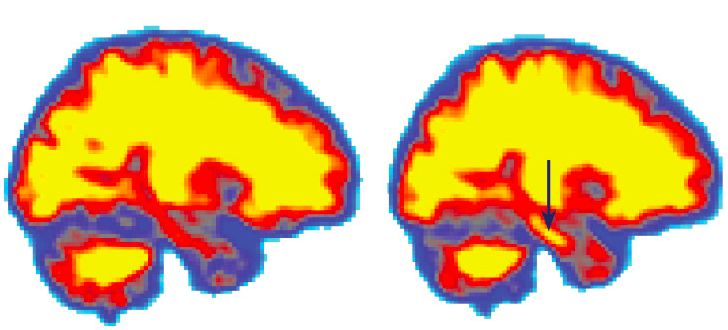

Levels of A-beta rose in a volunteer’s brain after sleep deprivation, shown by the arrow.

Amyloid beta is a protein that is generated as waste by neurons. Higher levels of A-beta are found in people suffering from Alzheimer’s. The body generally cleans up this protein, but this cleaning up process seems to be occurring during sleep. Thus, lack of sleep means inefficient cleaning up of A-beta, which eventually could lead to its accumulation in the brain’s pathways, causing Alzheimer’s.

A subgroup of 98 people in this study recorded their sleep quality. Of these, those who reported having slept poorly also had high levels of A-beta. In a different group of 101 people, analysis of spinal fluid was carried out. Here as well, people who had insufficient sleep showed A-beta plaques as well as tau protein and inflammation — again indicators of Alzheimer’s.

But for humans, it is difficult to conclusively say anything as the brain developments leading to Alzheimer’s occur over many decades. Study subjects will be willing to be give up sleep for a few days for making observations about developments in the brain, but it is not possible to deprive anyone of sleep for years to carry out research.

In a study published in Sleep, researchers measured A-beta levels in a group of 13 volunteers. The measurements were done for the first time after five days of good sleep, following which the participants were asked to cut back to four hours of sleep for five nights. Four of the volunteers went for eight days on four hours of sleep. However, A-beta levels did not show much difference, again pointing to a need for more research over longer stretches of time.